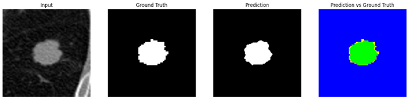

This section quantitatively evaluates the segmentation efficacy of CAAF-ResUNet across three boundary-aware loss configurations using the MEF-PN35 dataset, which consisted of 804 CT slices obtained from 35 patients at the University Medical Center Ho Chi Minh City. The results are summarized in Table 8, while Figure 3 illustrates the patch-wise distribution of Dice scores under three different boundary-aware loss configurations.

As shown in Figure 3, the Sobel- and Hausdorff-based configurations exhibited high segmentation stability, in most cases achieving Dice scores ≥ 80%. This indicates that the model predictions are spatially well-aligned with expert annotations. High Dice scores typically occur when nodules have well-defined boundaries and are accurately localized and segmented in both shape and position. In contrast, the Laplacian-based configuration showed greater variability, with a larger number of outlier cases falling below 80%—and some even below 50%—indicating potential instability when processing heterogeneous or low-contrast nodules in clinical CT scans.

From the aggregate results in Table 9, the Hausdorff configuration yielded the highest average Dice score (95.34 ± 5.08)%, highest sensitivity (95.40 ± 6.28)%, and lowest Miss Rate (4.60 ± 6.28)%.

Following the summary in Table 11, we present detailed visual comparisons for selected representative cases, each corresponding to a specific segmentation challenge. These cases are consistently labeled using the Challenge ID (CID) codes defined in Table 9 to facilitate cross-referencing between the summary and the case illustrations. Each table reports segmentation results across three loss configurations (Sobel, Laplacian, and Hausdorff) using five columns. Loss indicates the boundary loss formulation applied in each case, where Dice loss is combined with a boundary term computed using Sobel, Laplacian, or Hausdorff operators. The Segmentation Result column shows four images side by side: the input CT patch, the manual ground truth, the model prediction, and a color-coded difference map between ground truth and prediction. In this map, green indicates true positives, blue represents true negatives, red corresponds to false positives, and yellow denotes false negatives. The final column, Attention Map, presents Grad-CAM visualizations derived from one of the Adaptive Attention Fusion (AAF) layers in the encoder path. These maps illustrate the spatial focus of the model, with red/yellow regions indicating strong attention and lighter or neutral tones indicating lower activation. All six cases are presented in detail in Table 11, Table 12 and Table 13, providing a comprehensive qualitative analysis of how each loss configuration performs under specific segmentation challenges observed in real clinical data.